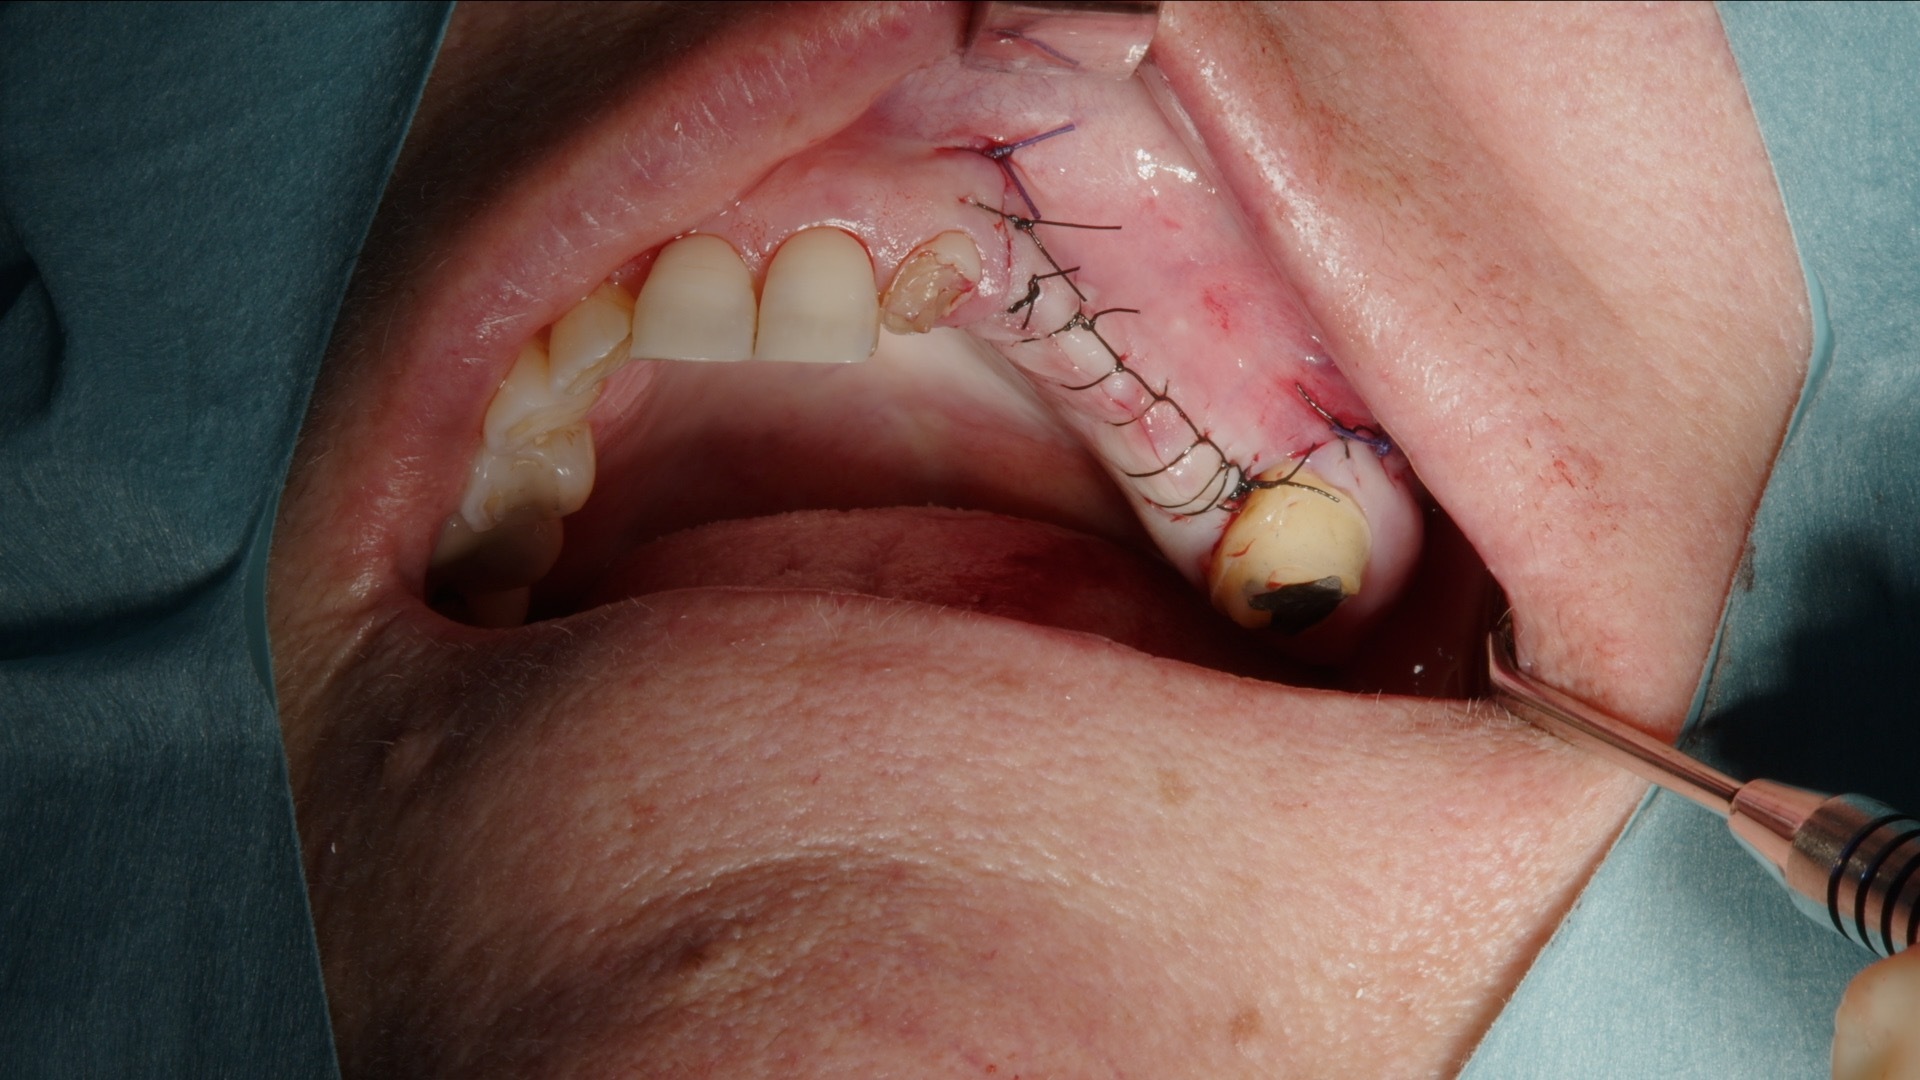

8. Suturering av lambå.

Efter utfyllnad täcks det laterala fönstret med Geistlich Bio-Gide kollagenmembran. Membranet fungerar som barriär mot mjukvävnadsinväxt och stabiliserar transplantatet under läkningsfasen. Därefter repositioneras lambån tensionfritt och sutureras noggrant.